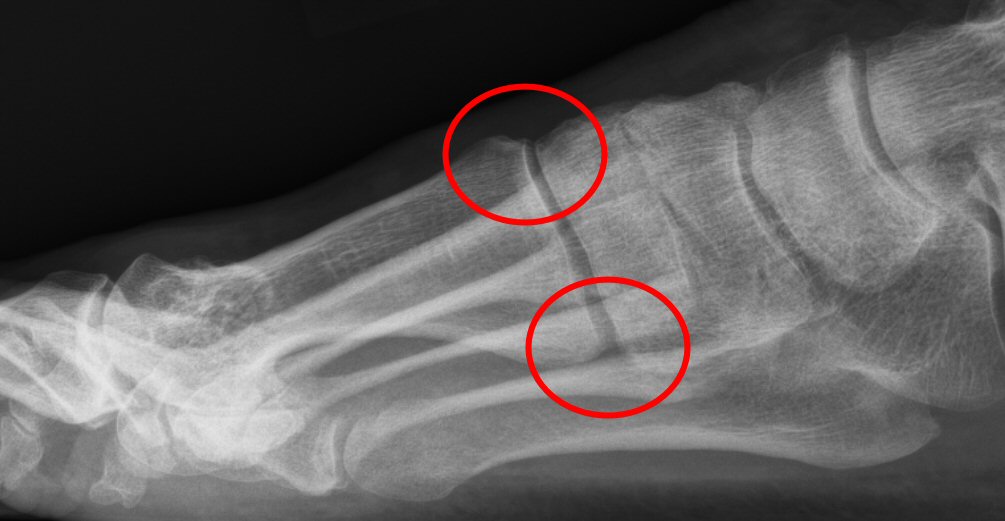

- Kontrollera att det finns röntgenbilder, helst med belastning.

Tecken till instabilitet i TMT1: minskad ledspringa dorsalt